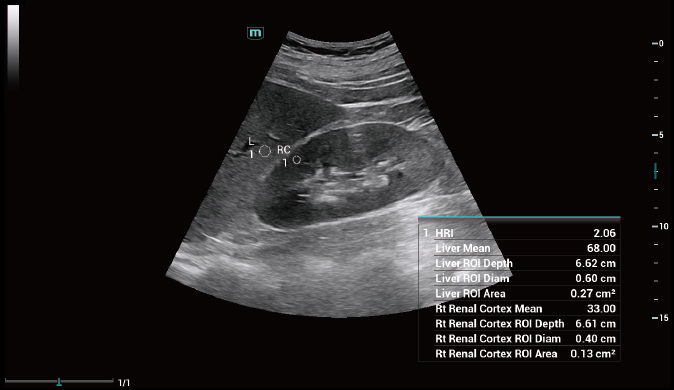

Für die Ultraschalltechnologie stellt die ZST+-Plattform einen bedeutenden Fortschritt dar, da sie statt der herkömmlichen Strahlformung die Kanaldatenverarbeitung verwendet. Diese bahnbrechende Innovation löst übliche Zielkonflikte zwischen räumlicher Auflösung, zeitlicher Auflösung und Homogenität des Gewebes auf, woraus sich eine beispiellose Bildqualität ergibt, die den Weg frei macht für unendlich viele Bildgebungslösungen.

Das Resona I8 weist vielfältige klinische Lösungen auf, die speziell für den jeweiligen Anwendungsbereich entwickelt wurden. Die Technologie baut auf einem tiefgreifenden Verständnis verschiedener klinischer Szenarien auf und bietet eine umfassende Serie fortschrittlicher Diagnoseinstrumente, beispiellose Intelligenz und präzise Analysen zur Verbesserung von Diagnosesicherheit, Qualitätskontrolle und Scaneffizienz.